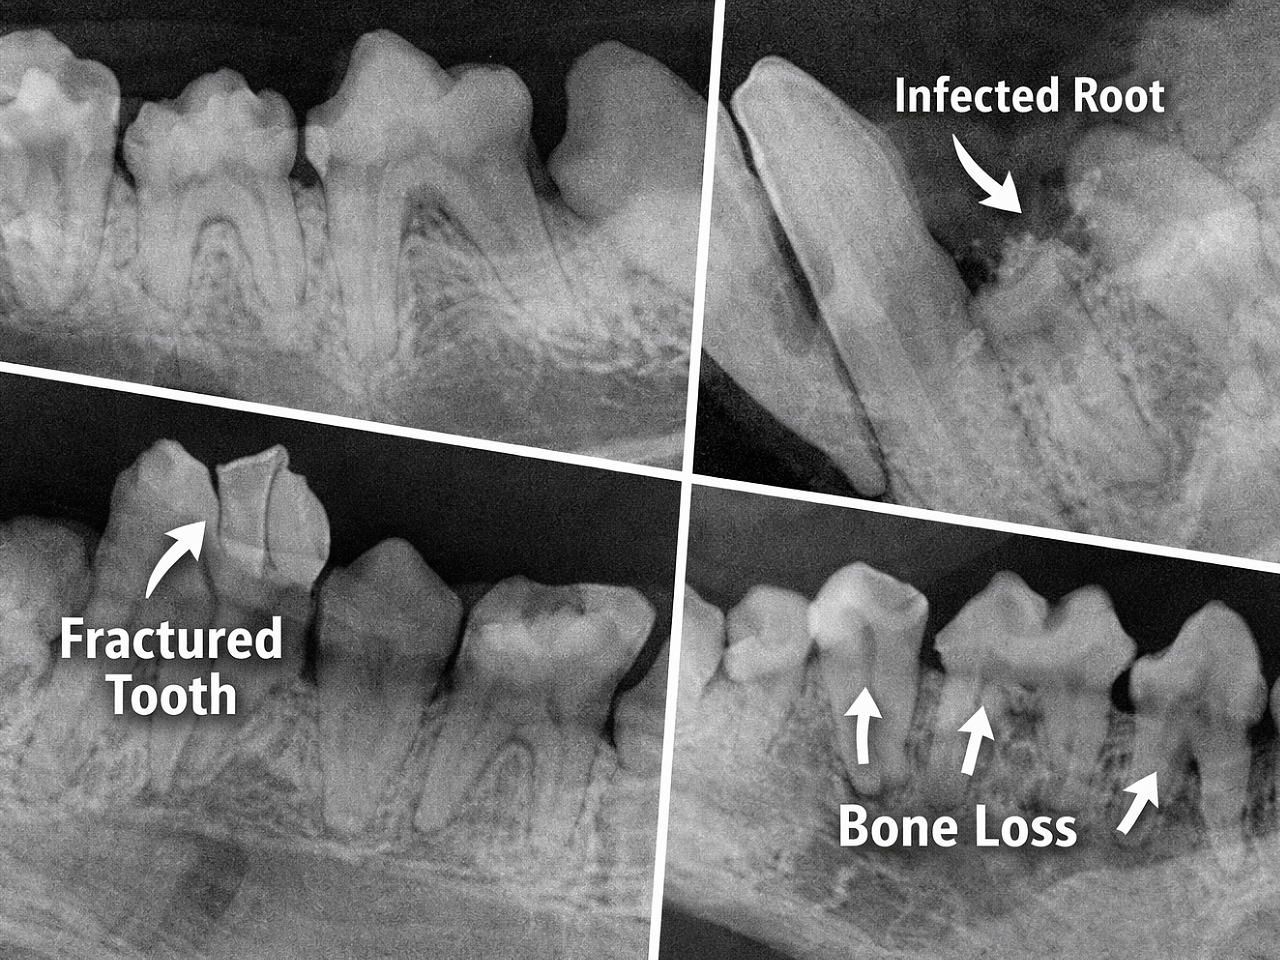

Dental radiographs are essential to complete the dental assessment and generate an acceptable therapeutic plan. Because 50% of each tooth is below the gum line, it is not possible to examine the entire tooth using any other method. We recommend full mouth dental radiographs for every pet and every dental procedure, just like your dentist does for you. Dental radiographs will uncover any hidden painful disease, such as root abscesses, root fractures, severe bone loss of the jaw and cystic lesions, so that they can be corrected during the procedure. Dental radiographs are especially imperative in pets due to their high tolerance for pain and inability to communicate it.

Advanced dental imaging is taken of every tooth in the mouth to discover problems, such as retained roots, enamel defects, root abscesses and bone loss due to infection.